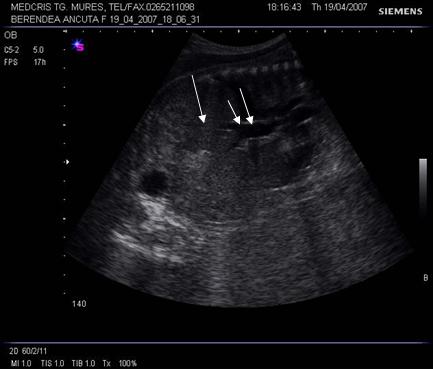

Fig. nr. 241. Fat cu hidrops nonimun , cu insuficienta cardiaca si bradicardie , la 28 sapt., se remarca hepatomegalia ( sageata ) si dilatatia venei cave inferioare

( doua sageti )